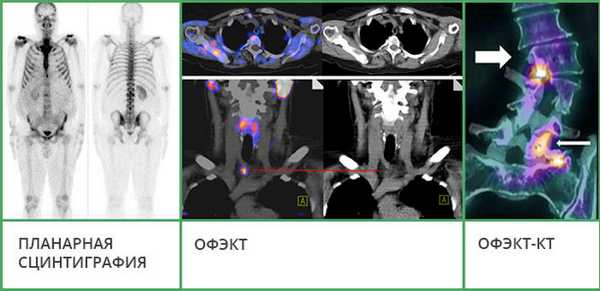

- Планарная сцинтиграфия - наиболее простая методика. Позволяет получать двухмерные снимки, как во время рентгенографии, на которых видно распределение радиофармпрепарата. Этот вид исследования часто используют, чтобы обнаружить в костях первичную злокачественную опухоль или метастазы.

- Однофотонная эмиссионная компьютерная томография (ОФЭКТ) позволяет получить серию смежных двухмерных изображений, на которых также визуализируется распределение радиоактивного индикатора.

- ОФЭКТ-КТ - наиболее информативная методика. Во время исследования данные сцинтиграфии совмещают со снимками, полученными с помощью КТ. Это позволяет получать трехмерные изображения, судить не только о патологических изменениях в костях, но и о точной локализации очагов.

Повышение накопления различных препаратов на основе фосфата в области КПС при сакроилеитах продемонстрировано в ряде исследований [2, 11]. Так, в исследовании Ian M. было показано, что повышенное накопление РФП в КПС может предшествовать появлению рентгенологических признаков сакроилеита у пациентов с определенным анкилозирующим спондилитом. Кроме того, метод позволяет выявить сакроилеит у пациентов с другими формами заболеваний суставов и позвоночника [11]. В исследовании Rothwell R.S. et al. количественная сцинтиграфия КПС позволила выявить признаки сакроилеита у 40% женщин с хроническими болями в нижней части спины. При этом показано, что в большинстве случаев эти сакроилеиты регрессировали со временем [12]. Усовершенствованная радионуклидная методика ОФЭКТ/КТ позволяет дополнительно улучшить эффективность и точность выявления сакроилеита у пациентов со спондилоартритами. Значительным преимуществом сцинтиграфии является способность с высокой специфичностью и чувствительностью выявлять целый ряд поражений позвоночника, которые, как правило, приходится дифференцировать в реальной практике при болях в спине. К таким заболеваниям и состояниям можно отнести костные метастазы (чувствительность - 74-97%, специфичность - 64-93%), спондилиты (чувствительность - 90%, специфичность - 78%); анкилозирующий спондилит (чувствительность - 26-45%, специфичность - 100%) [13]. Кроме того, с высокой точностью могут диагностироваться дисциты [14], компрессионные переломы позвонков [14]. Таким образом, сцинтиграфические методы (планарная сцинтиграфия, ОФЭКТ, ОФЭКТ/КТ) могут использоваться при дифференциальной диагностике болей в спине, особенно боли воспалительного типа, а также при подозрении на сакроилеит, анкилозирующий спондилит, инфекционные спондилиты.